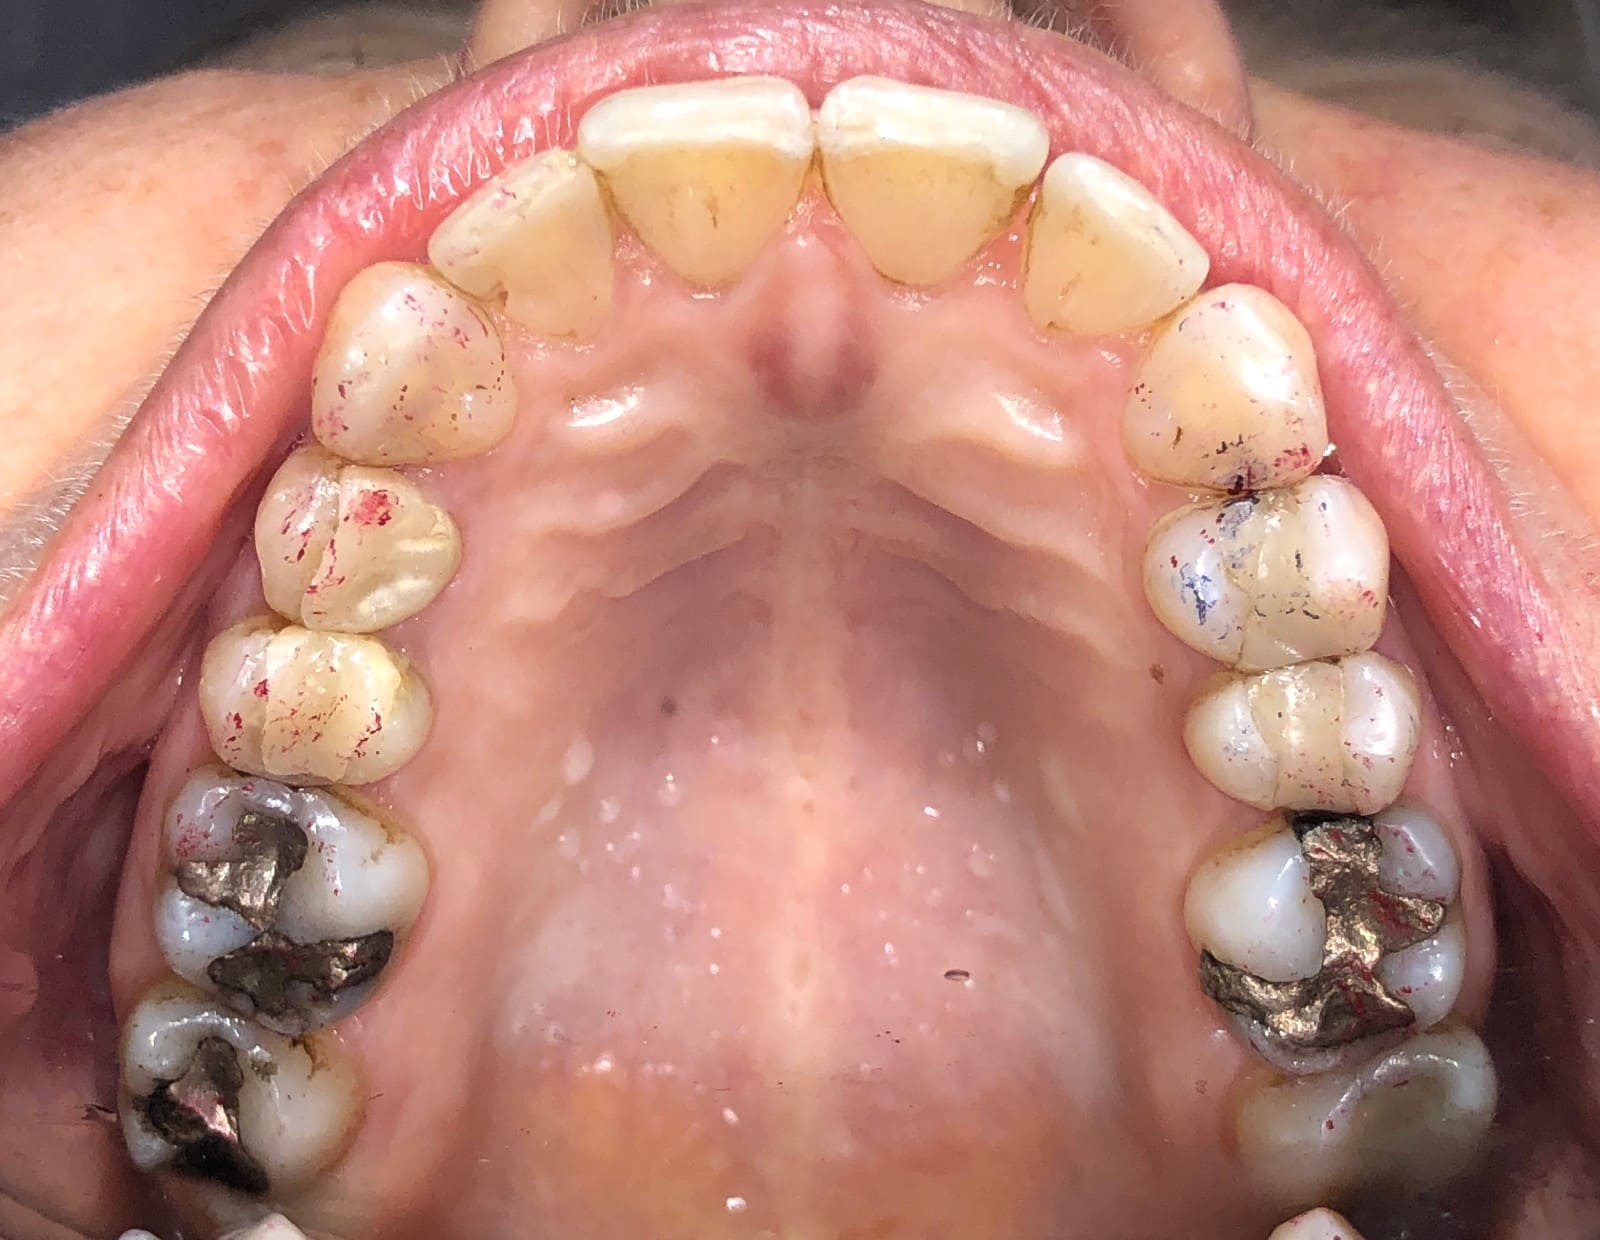

Initial